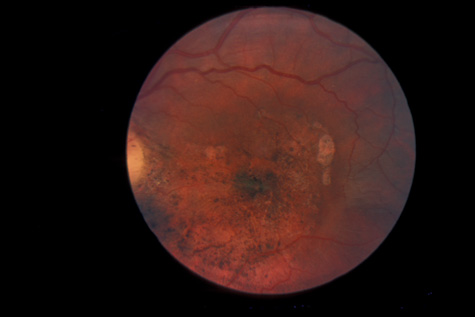

tomography. Eur J Ophthalmol 13:818, 2003 67. Blight R, Hart JCD. Structural changes in the outer retinal layers following blunt mechanical

nonperforating trauma to the globe. An experimental study. Br J Ophthalmol 61:573, 1977 68. Mansour AM, Green WR, Hogge C: Histopathology of commotio retinae. Retina 12:24, 1992 69. Sipperley JO, Quigley HA, Gass JDM: Traumatic retinopathy in primates, the explanation of commotio retinae. Arch Ophthalmol 96:2267, 1978 70. Friberg TR: Traumatic retinal pigment epithelial edema. Am J Ophthalmol 88:18, 1979 71. Bastek JV, Foos RY, Heckenlively J: Traumatic pigmentary retinopathy. Am J Ophthalmol 92:621, 1981 72. Crouch JER, Apple DER: Posttraumatic migration of retinal pigment epithelial melanin. Am J Ophthalmol 78:251, 1974 73. Al-Abdulla NA, Thompson JT, Sjaarda RN: Results of macular hole surgery with and without epiretinal dissection